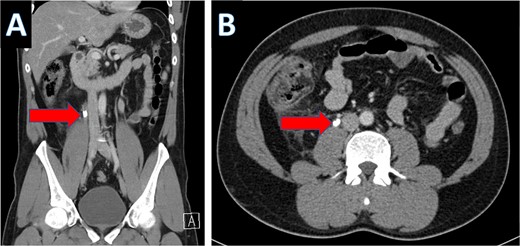

Multiple tiny obstructive stones were also noted bilaterally. The appendix measured approximately 1.4 cm in maximum caliber, with an appendicolith present within the appendiceal lumen (Fig. 3a). Significant surrounding fat stranding was noted around the appendix, and multiple enlarged lymph nodes with signs of reactive inflammation were seen adjacent to the cecum (Fig. 3b).

Coronal CT scan showing appendicolith (A) and axial CT showing appendicitis (B).